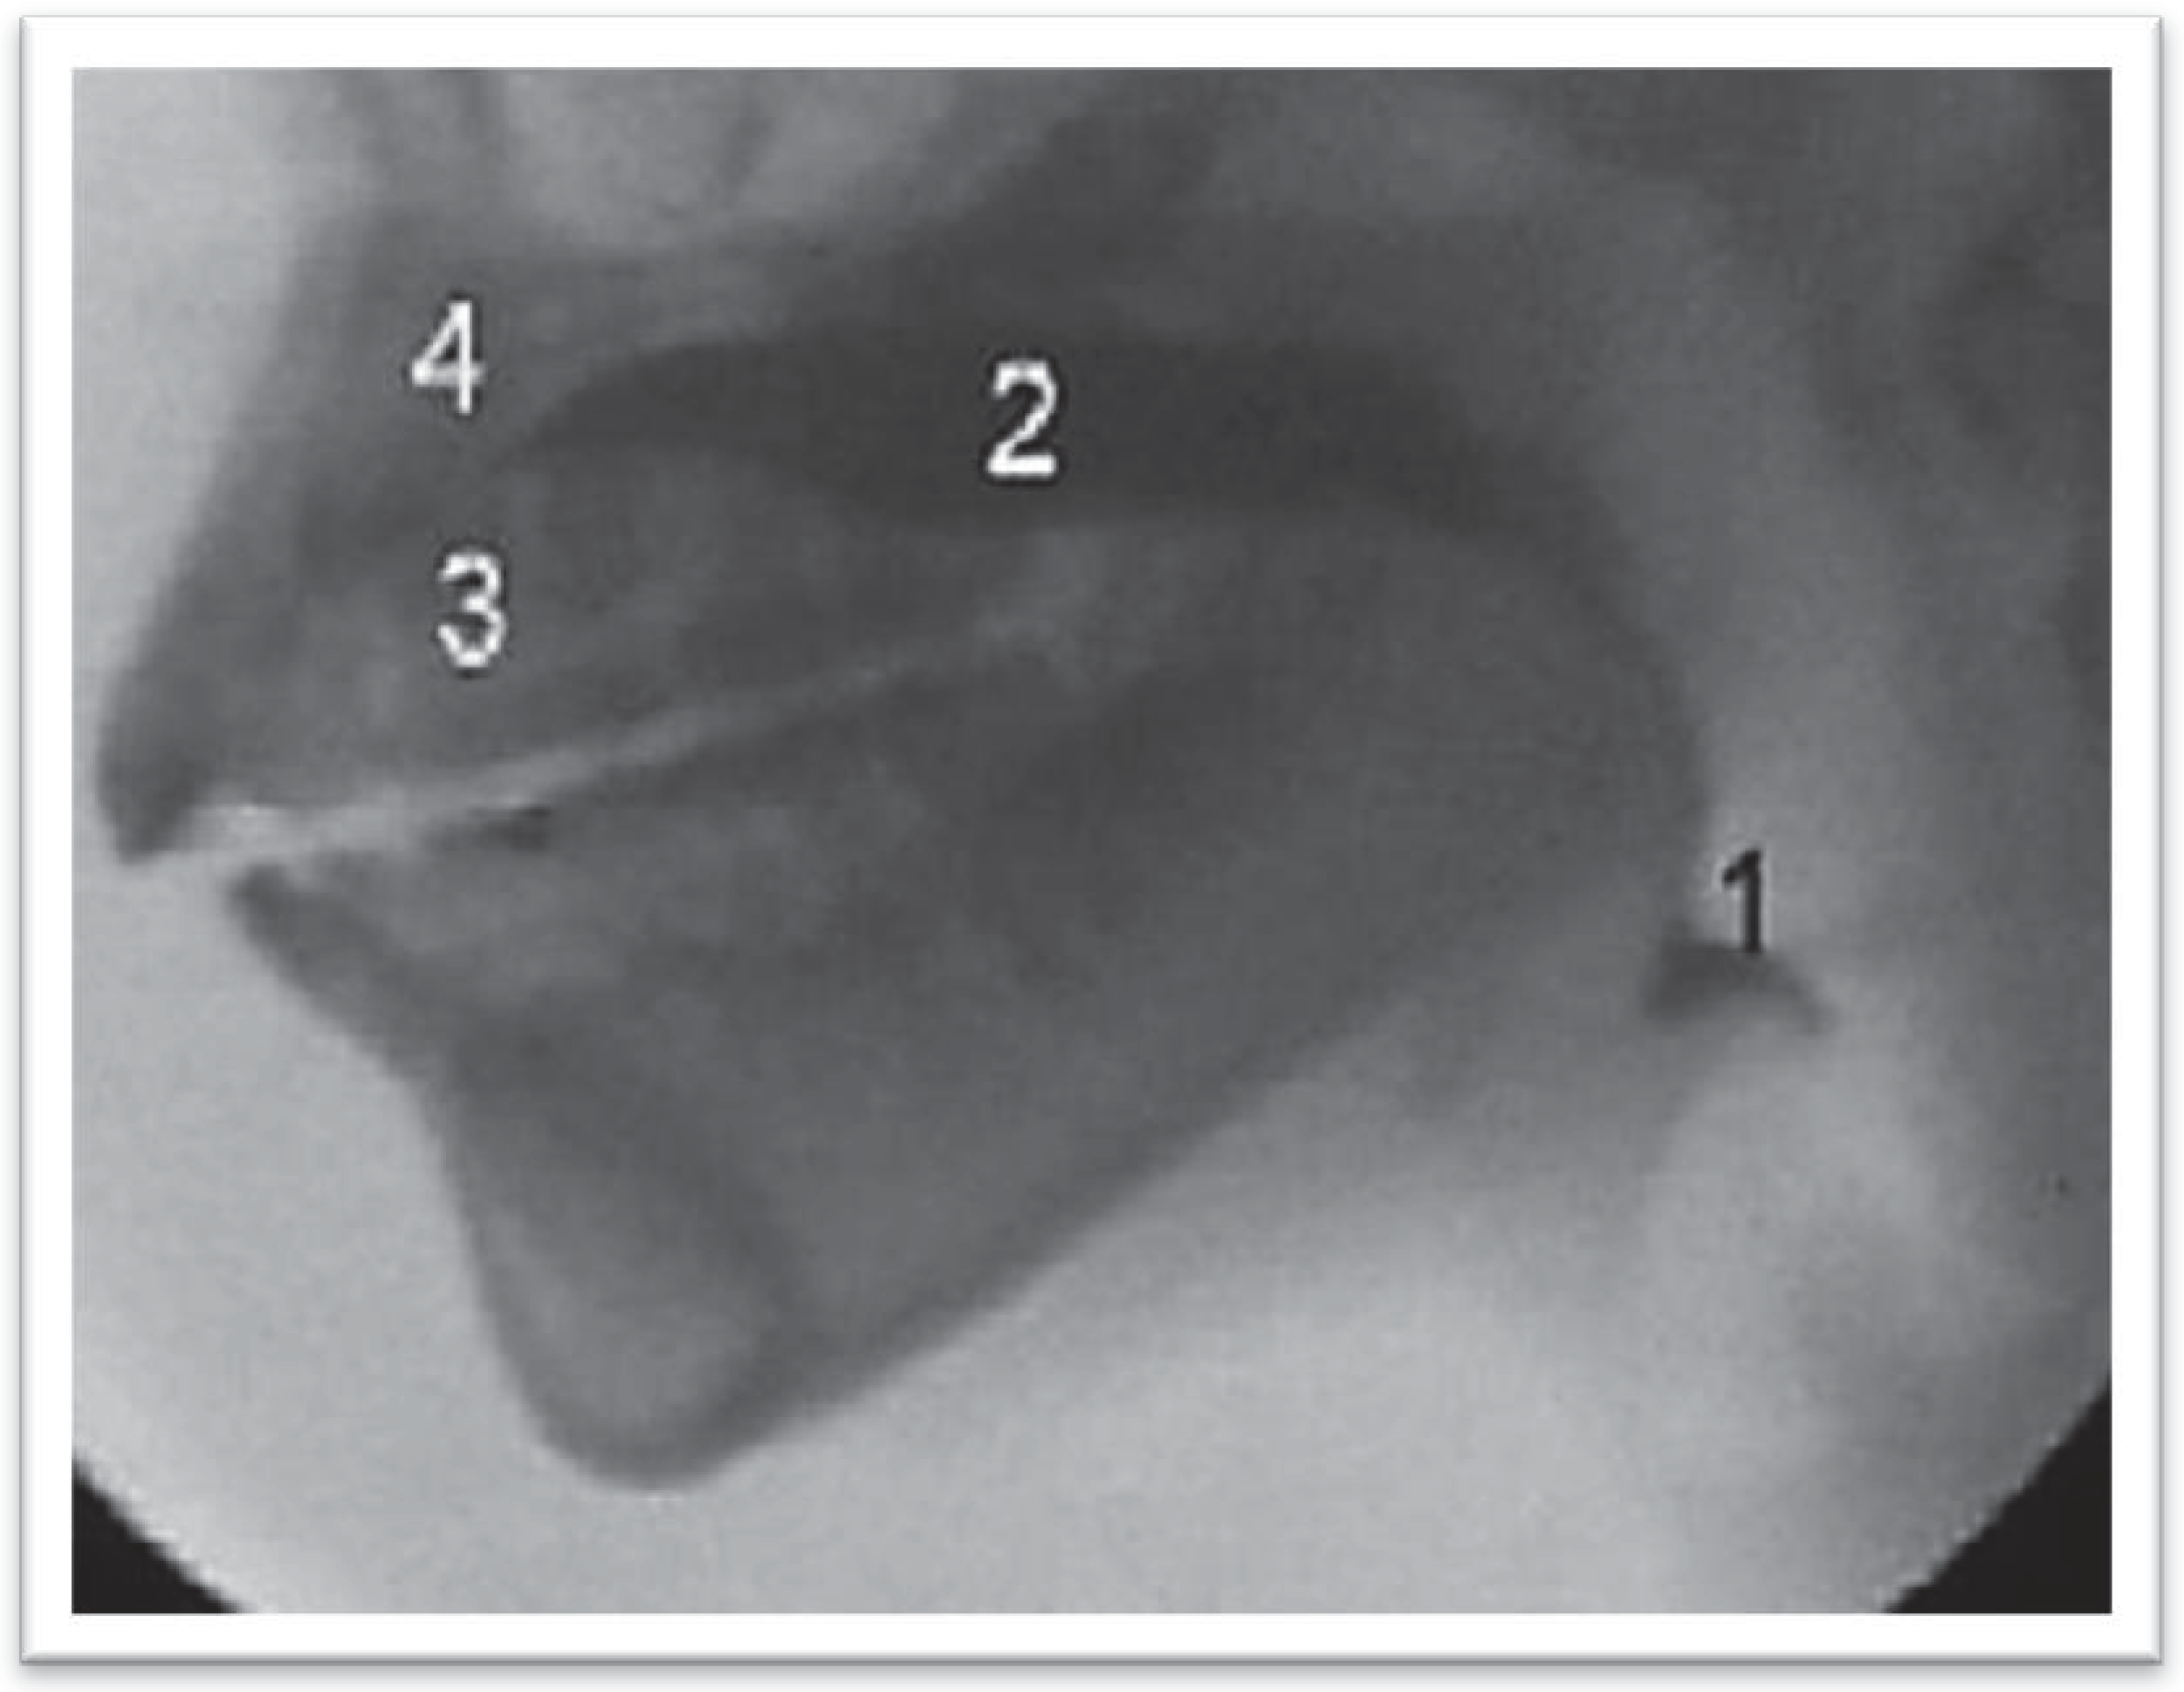

Figure 3. Videofluoroscopic exam on patient with dental malocclusion Angle Class II type, with adaptation defined as Type 2 in two stages during Oral Ejection Phase. 1—Part of the contrast that escaped to the vallecula. 2—Remaining contrast to be ejected; 3, 4—Anterior part of the dorsal surface of the tongue, against the hard palate.